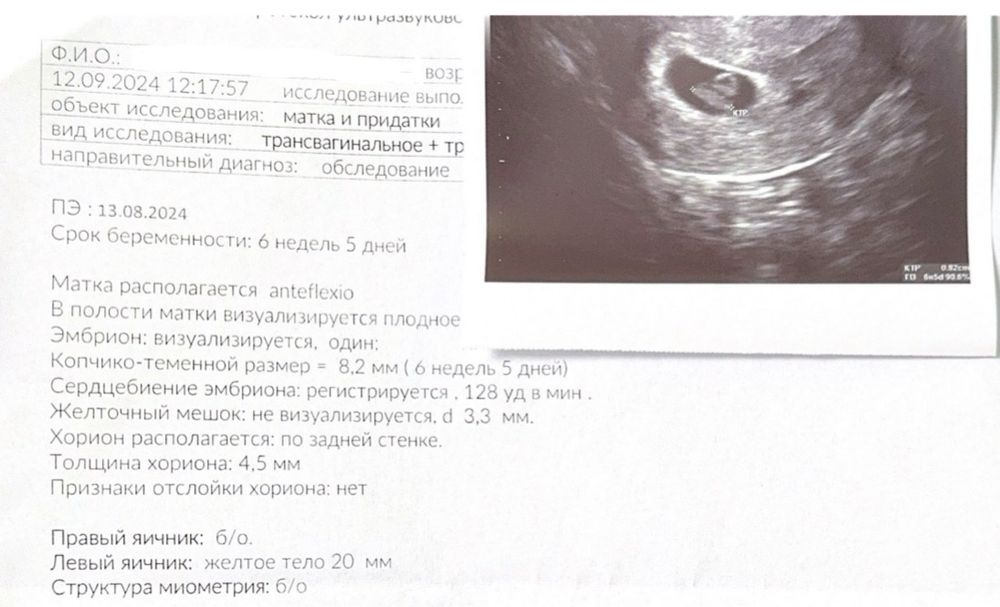

на 23 дпп - пя 14, жм 3 на 30 дпп - пя 25, жм 6, ктр 8, сердцебиение

Анна, спасибо 🙏🏻 Меня тревожит скорее не сам КТР, а то что с 24 дпп до 30 дпп динамика кажется медленной

Не поленилась нашла свое на 27 дпп ,ктр 0,71 Изображение

квитка, ну вот у тебя на 30 дпп, КТР наверное был уже 10

У меня с дочей такой же ктр был в 6+5 недель)

По сроку 6 недель 5 дней размер ктр отличный 😄 я бы не переживала раньше времени. Тем более всегда есть вероятность погрешности в измерении.

Марго , спасибо 🙏🏻 Меня тревожит скорее не сам КТР, а то что с 24 дпп до 30 дпп динамика кажется медленной